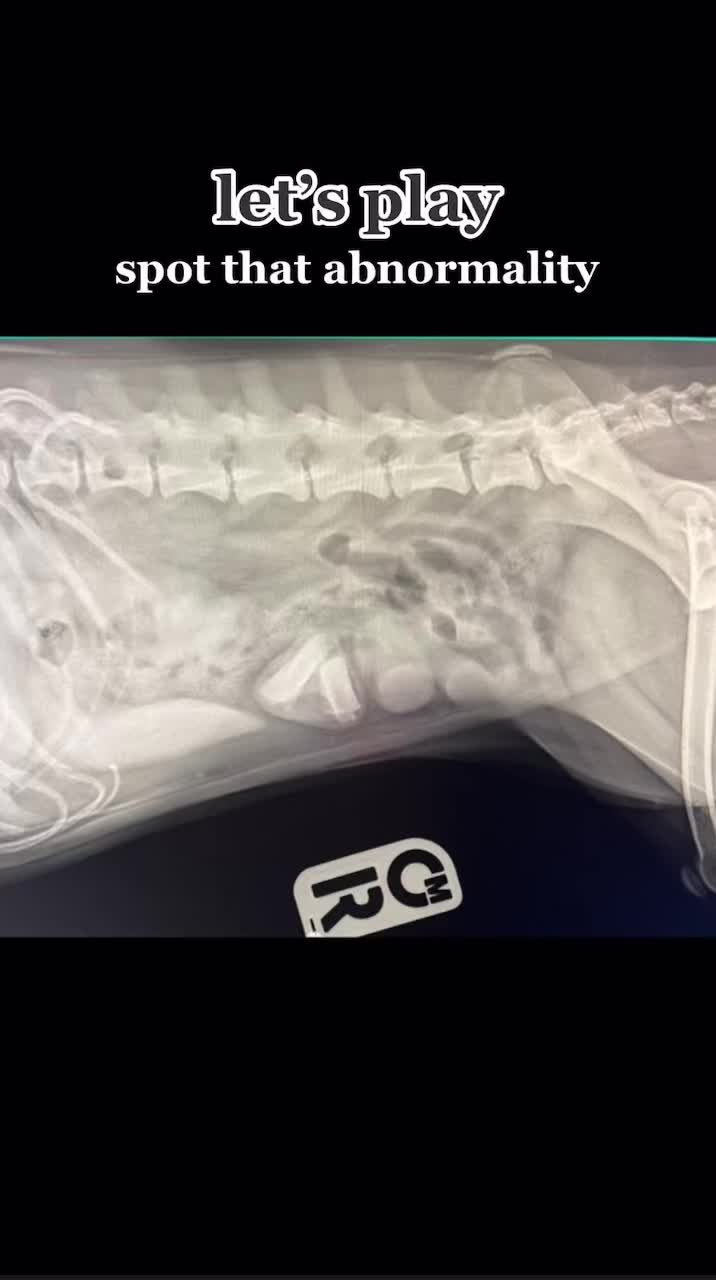

this doggo presented for intermittent vomiting over 1 week… what do you see? 👀🐶 #vetmed #vetcases #vetcase #vetlife #petparent #dogparent #vetmedlife #vetmedicine #prevet #vetnurse #vettechlife